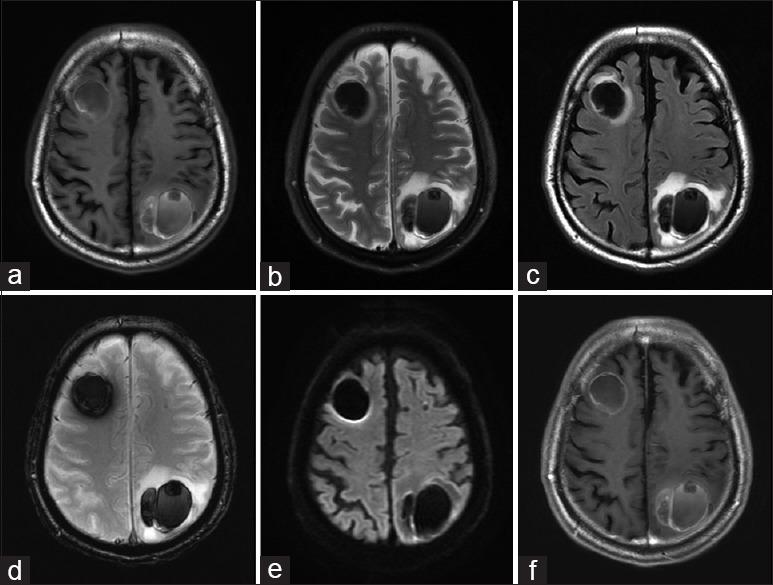

The brain metastasis of angiosarcoma is very rare, and little is known about its clinical features or therapeutic strategy. A 74-year-old male was hospitalized for disturbance of consciousness. Radiological examination revealed multiple cerebral hematomas. Gadolinium contrast-enhanced magnetic resonance imaging showed no significant enhancement at any of the lesions. To detect a suspected metastatic brain tumor or abscess, a full-body scan was performed but revealed only a poorly enhanced mass in the removal cavity caused by thoracoplasty in the left upper chest. After admission, a cascade of expansion of those hematomas occurred in the right frontal, left parietal, and right temporal lobes, and each lesion thus had to be sequentially removed by craniotomies. The pathological diagnosis of the right frontal lesion was an abscess with hematoma. However, a malignant vascular tumor was highly suspected because of many CD31(+)/Ki-67(+) cells in the left parietal lesion. A mass in the scar caused by thoracoplasty was suspected to be the primary lesion, and brain metastasis of angiosarcoma was finally diagnosed. Whole-brain irradiation and systemic paclitaxel administration were performed, and a complete response for the brain lesions was obtained for 22 months; the patient then died of an intratracheal hemorrhage. This case represents the first report of multiple brain metastases from pyothorax-associated angiosarcoma accompanied by sequentially and gradually expanding hematomas, as well as the first case with the control of metastatic brain lesions for over 1 year after the onset of neurological symptoms. Control of the lesions could be achieved by their total removal with complete hemostasis, as well as additional radio- and chemotherapy.

血管肉瘤脑转移非常罕见,其临床特征或治疗策略鲜为人知。一名74岁男性因意识障碍入院。影像学检查发现多处脑血肿。钆增强磁共振成像显示任何病变均无明显强化。为检测疑似转移性脑肿瘤或脓肿,进行了全身扫描,但仅发现左上胸部胸廓成形术切除腔内有一个强化不佳的肿块。入院后,右额叶、左顶叶和右颞叶的血肿相继扩大,因此每个病变都必须通过开颅手术依次切除。右额叶病变的病理诊断为血肿性脓肿。然而,左顶叶病变中存在许多CD31(+)/Ki-67(+)细胞,高度怀疑为恶性血管肿瘤。胸廓成形术瘢痕处的肿块被怀疑是原发灶,最终诊断为血管肉瘤脑转移。进行了全脑照射和全身紫杉醇给药,脑病变获得了22个月的完全缓解;患者随后死于气管内出血。本病例代表了第一例脓胸相关性血管肉瘤多发脑转移并伴有血肿依次逐渐扩大的报告,也是第一例神经症状出现后转移性脑病变得到控制超过1年的病例。通过彻底止血的完全切除以及额外的放疗和化疗可以实现病变的控制。